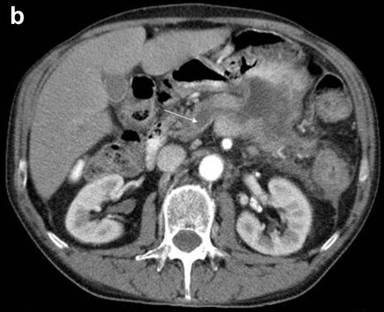

A 64-year-old man, with past medical history of high blood pressure and type 2 diabetes was evaluated in our outpatient clinic due to anemia. He also complained about mild dyspepsia and low-back pain over the last 18 months. Conventional blood tests showed microcytic anemia. Tumor markers were normal, except for CA 19-9 203 U/mL (reference range: 0-39 U/mL). A contrast-enhanced computed tomography (CT) scan of the abdomen showed a 12x7 cm inhomogeneous, low-density mass originating from the body and tail of the pancreas. The mass invaded the posterior gastric wall, the splenic flexure of the colon and the spleen. The superior mesenteric artery and the celiac axis were not involved; however, the splenic artery was amputated at its origin (Figure 1a). The Wirsung duct at the pancreatic head was enlarged (Figure 1b), with splenic vein thrombosis, segmental portal hypertension and esophageal varices.

Figure 1. Preoperative contrast-enhanced CT-scan at the celiac axis level. a. A large low-density mass in the pancreatic body and tail infiltrating the posterior gastric wall, the splenic flexure of the colon and the spleen. The amputation of the splenic artery is evident. b. Dilated main pancreatic duct (white arrow). |